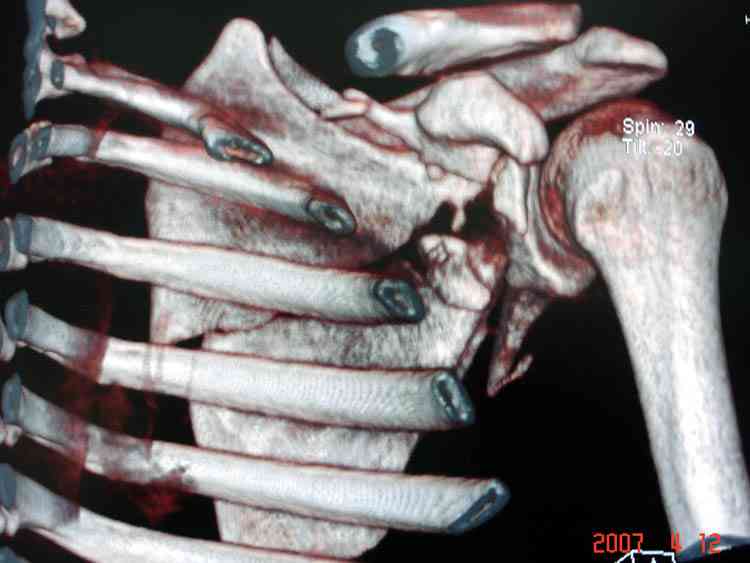

На снимке (№6 компьютерная томограмма и 3D №7) перелом клювовидного отростка.

Передним дельтопекторальным Bankart доступом намного легче провести фиксация отростка, но тогда репозиция и фиксация колонн затрудняется, поэтому был применен стандартный Judet задний доступ.

Репозицию смогли сделать пальцами через щель между

шейкой и телом лопатки (последний 3D снимок)

Двумя шурупами сзади на пластине (вместе шайбы)

провели удержание репозиции, а фиксацию провели

следующим косым шурупом.

Последующие этапы на снимках.

К-томографические и Трехмерные(3D)снимки крайне важны для определения внутрисуставных переломов и классификации.